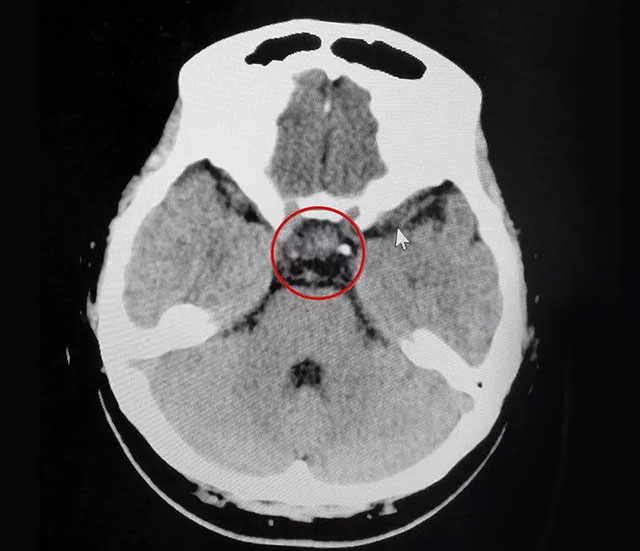

▲ 术后CT影像显示:肿瘤切除干净

“没什么感觉,就像打了个盹。”手术一周后,刘女士恢复得不错,饮食起居正常,月经逐渐恢复正常,各项内分泌指标也恢复正常。目前,刘女士已经出院,她将有望圆了自己的“小棉袄”心愿。